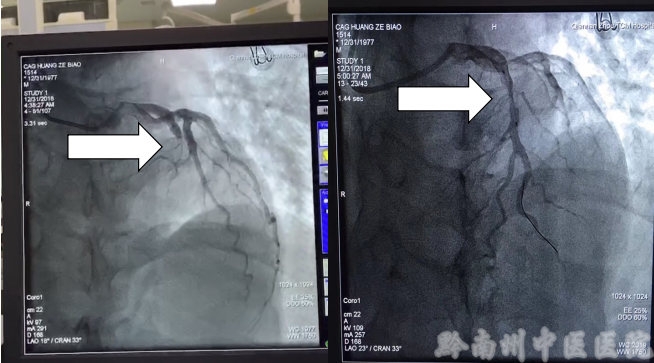

据了解,患者黄先生是重庆来都匀工作的异乡人,在这寒冬里远离故土,因为没有开通医保,家人一筹莫展,在生死面前黔南州中医院胸痛中心又一次迅速开通绿色通道,立即完善心电图、抽血化验等检查,确诊心肌梗死后立即着手术前准备,待家属时间允许后再办理入院手续。10分钟内迅速完成以上程序,患者从就诊到进入手术室(导管室)仅仅18分钟。该患者自急诊科至手术室球囊扩张开通堵塞血管仅用时46分钟。目前该中心2018年成功开通急性心梗闭塞血管的患者近50例,均是先诊疗后付费,没有一例是先缴足费用才手术的,也没有一例因为费用耽误治疗。这次“先诊疗后付费”再次得到了体现。以上工作的顺利进行也得益于黔南州中医医院院领导对该项工作的重视,才让该院团结协作、感恩奋进的心内科团队义无反顾、全力以赴、没有后顾之忧的去救治病人。